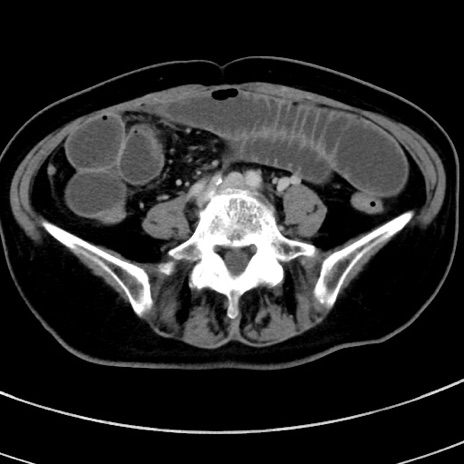

症例9(横断像)

【症例】 60歳代女性

【主訴】むかつき、みぞおちの痛み

【現病歴】3日前よりむかつきがあり、食事がとれない。

【既往歴】糖尿病

【身体所見】発熱なし、心窩部圧痛軽度あるも、腹膜刺激症状なし。

【データ】WBC 7400、CRP 1.92